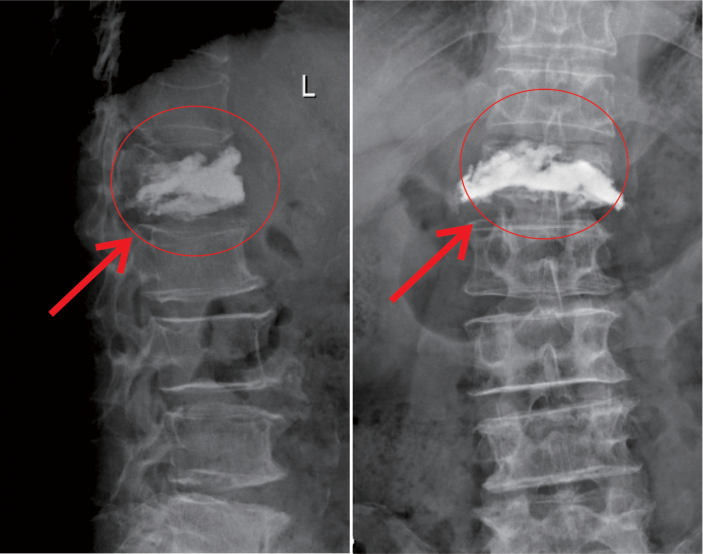

△術中注入骨水泥約11ml

在我院先進的術中三維CT引導下,杜教授确定L1雙側椎弓根進針點,娴熟地将穿刺針穿入L1椎體,經穿刺針建立通道将約11ml骨水泥注入坍塌的椎體中。術中監視,注入的骨水泥逐漸支撐起原本壓縮空洞的椎體。骨水泥凝固後,病變的椎體迅速恢複了承重能力。手術持續約40分鍾,開展非常成功,術後老人的疼痛馬上消失,翻身也無疼痛,第二天就能使用助步器下地行走。